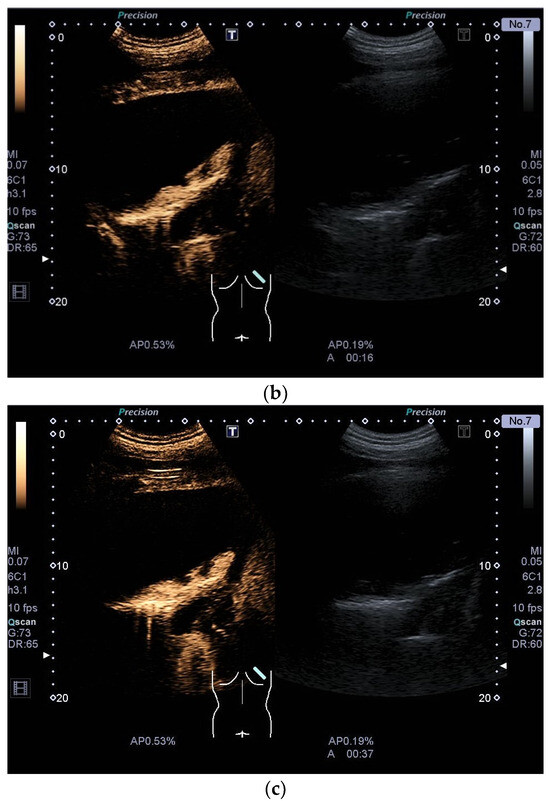

| Benign solitary fibrous tumor | Smoothly bordered, hypoechoic. Examples with a nodular shape have been described. Larger tumors can have cystic parts. With few data and based on our example, the solid parts are hyper-enhanced in CEUS. |

| Schwannoma | Round or oval, smoothly bordered, hypoechoic. Cystic parts are typical, especially in larger tumors. In CEUS, the solid parts are hyper-enhanced. |